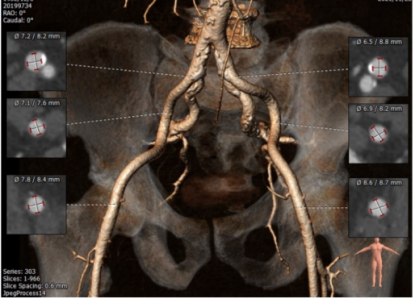

主动脉CT

瓣环平均直径:22.9mm

左室流出道平均直径:23.2mm

瓦士窦大小

横位心:50度

主动脉弓部角度平缓

入路条件尚可